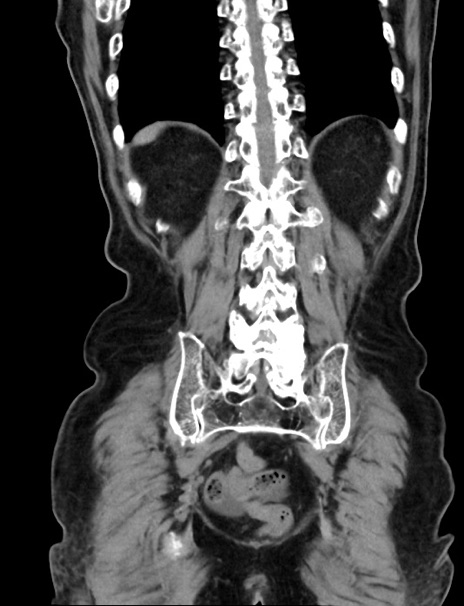

症例33(冠状断像)

【症例】70歳代 女性

【主訴】心窩部痛

【現病歴】延髄病変の精査・加療にて神経内科入院中。本日より心窩部痛あり。

【身体所見】右下腹部を中心に圧痛と反跳痛あり。

【データ】WBC 10900、CRP 0.02